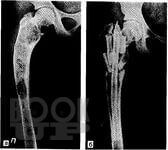

В учебном пособии подробно освещены вопросы эмбриогенеза трубчатых костей, нарушения их развития и формирования, дана подробная классификация нарушений дизонтогенеза. Описаны основные нозологические формы дизонтогенетических нарушений, наблюдаемых в клинической практике. Освещены вопросы кровоснабжения длинных трубчатых костей и репаративной регенерации при их переломах.